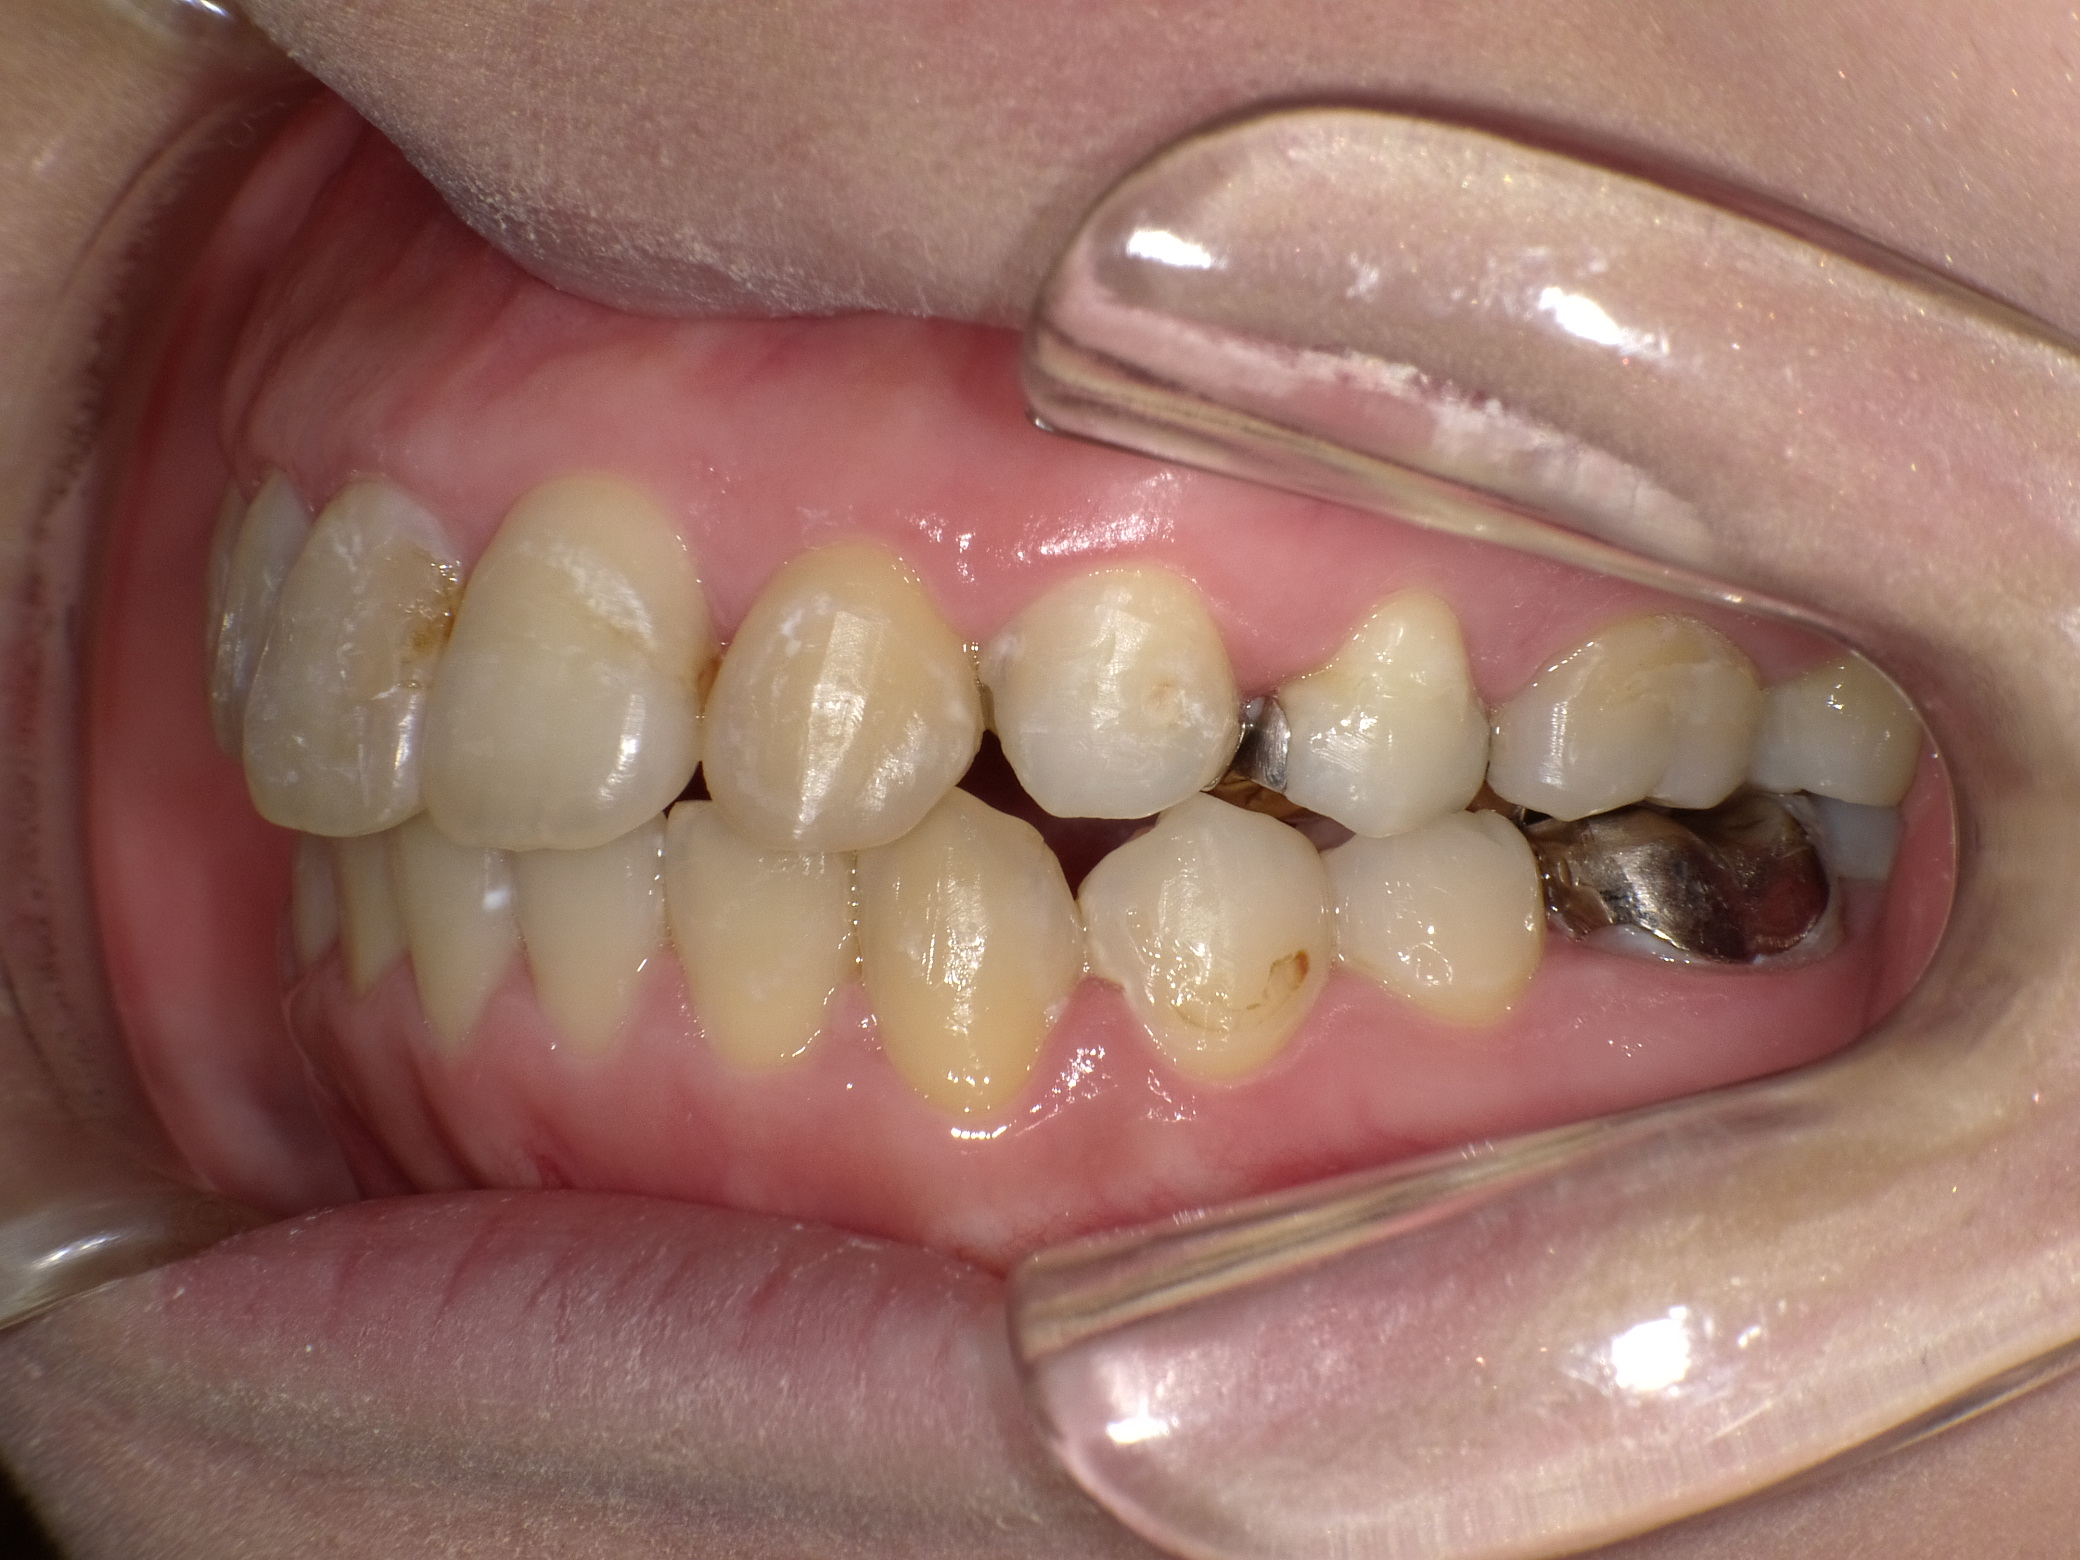

| 治療期間 | 2021年4月18日 〜2022年10月16日 |

|---|---|

| 治療費用 | 約770,000円 |

| 抜歯有無 | 抜歯あり |

| 矯正箇所 | クリアブラケット矯正 |